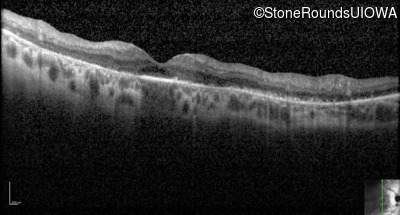

Optical Coherence Tomography - Right - 20/80

Exemplar / OCT Stack